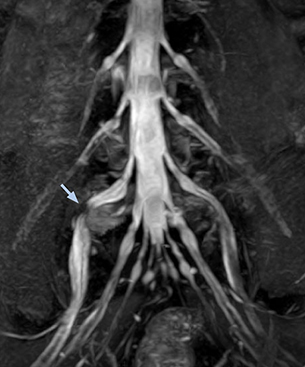

At Northern Fukushima Medical Center in Japan, excellent MRI visualization of nerves helps support confident diagnoses and informs surgical treatment decisions for patients with lower limb symptoms. MRI technologist Tanji and orthopedic surgeon Dr. Yabuki share how direct nerve visualization with the 3D NerveVIEW method adds information when diagnosing atypical herniations. The additional insights changed their way of working and benefit their patient care, as illustrated by some clinical examples.

“In patients with lower extremity neurological symptoms, NerveVIEW helps us to determine the disease matching the patient’s symptoms by directly visualizing the nerves. We use the sequence mainly, when there is suspicion of intraforaminal stenosis, extraforaminal stenosis or lateral disc herniation, which is often based on routine T2- and T1-weighted images. Additionally, the excellent depiction of the course of nerves makes NerveVIEW a good navigator when applying treatment such as block therapy or surgery.”

“In such case, we would then browse through axial T2-weighted MR images slice by slice and mentally reconstruct the actual situation based on both radiculography and MRI. Fortunately, NerveVIEW can now very well show nerve courses and presence of nerve compression or edema in one single image series.” “We have often seen NerveVIEW directly depict details of the nerve compression that were not observed by radiculography. Therefore, we think that with NerveVIEW we can reduce the number of invasive examinations, especially for some patients with lumbar plexus symptoms.”

“Before NerveVIEW, diagnosis by MRI alone was sometimes difficult, unless there was a strong suspicion based on clinical symptoms,” says Shoji Yabuki, MD, DMSc, Orthopedic surgeon at Fukushima Medical University School of Medicine. “This is why we routinely perform selective lumbosacral radiculography (nerve root block) and x-ray in such cases. However, radiculography can only depict nerves as far as the contrast agent reaches. When a nerve is distorted by compression, the contrast agent will not pass through this compressed area, preventing us from evaluating the full nerve compression.”

The key concept in MR neurography, Dr. Yabuki stresses, is the ability to directly visualize spinal nerves, versus inferring the presence of pathology indirectly. “Before NerveVIEW, we estimated compression of the nerve by looking for the presence or absence of fat signal on other MR images,” he says.

“For example, in sagittal images, when the presence of fat is observed in the intervertebral foramen, it suggests that there is a margin around the nerve. Similarly, the absence of fat indicates that the nerve is being compressed. So, we used to deduce nerve compression indirectly. With NerveVIEW, however, we can observe the condition of the nerves directly, regardless of the presence or absence of fat. We always prefer such direct observation of anatomy over having to make an inference about it.”

“Although symptoms of typical disc herniation and atypical hernia are very similar, the actual site of herniation is different. It is therefore important to characterize the nerve’s condition both inside and outside of the intervertebral foramina. “Conversely, if we see no abnormality in NerveVIEW, we can assume at least that there is no severe condition that requires surgery. Like this, it can help us avoid unnecessary surgery. NerveVIEW can have a tremendous impact in this way.”

“NerveVIEW is really useful for those cases where a nerve disorder is strongly suspected based on the clinical examination but our regular MRI images do not show any findings. These atypical herniations and spinal canal stenosis, occurring in 5% to 15% of the total lumbar herniation/stenosis cases are our main target when using NerveVIEW,” says Dr. Yabuki.